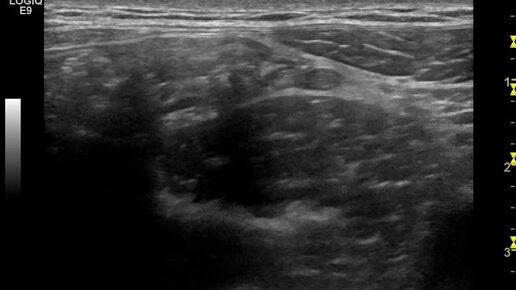

Ультразвуковая визуализация неизмененного аппендикса

Ультразвуковые находки от врача УЗД Зорина Я.П.